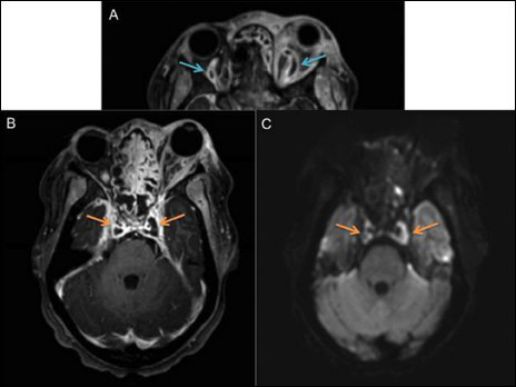

行头部和眼眶CT(图2)和MRI/MRV检查(图3),影像学显示双侧眼静脉充盈缺损和双侧合并低强化区,扩散受限,与海绵窦血栓形成表现相一致。同时,请耳鼻喉科、神经外科及传染科会诊。行鼻内镜手术及拔牙,术中行血液及鼻窦培养,术后立即全身抗凝。左眼给予布鲁莫尼丁,每日3次。

图3. 头部及眼眶MRI显示双侧眼静脉充盈缺损(a,蓝色箭头),双侧低强化融合区增加(b,橙色箭头),双侧限制性弥散(c,橙色箭头),与海绵状窦血栓形成一致